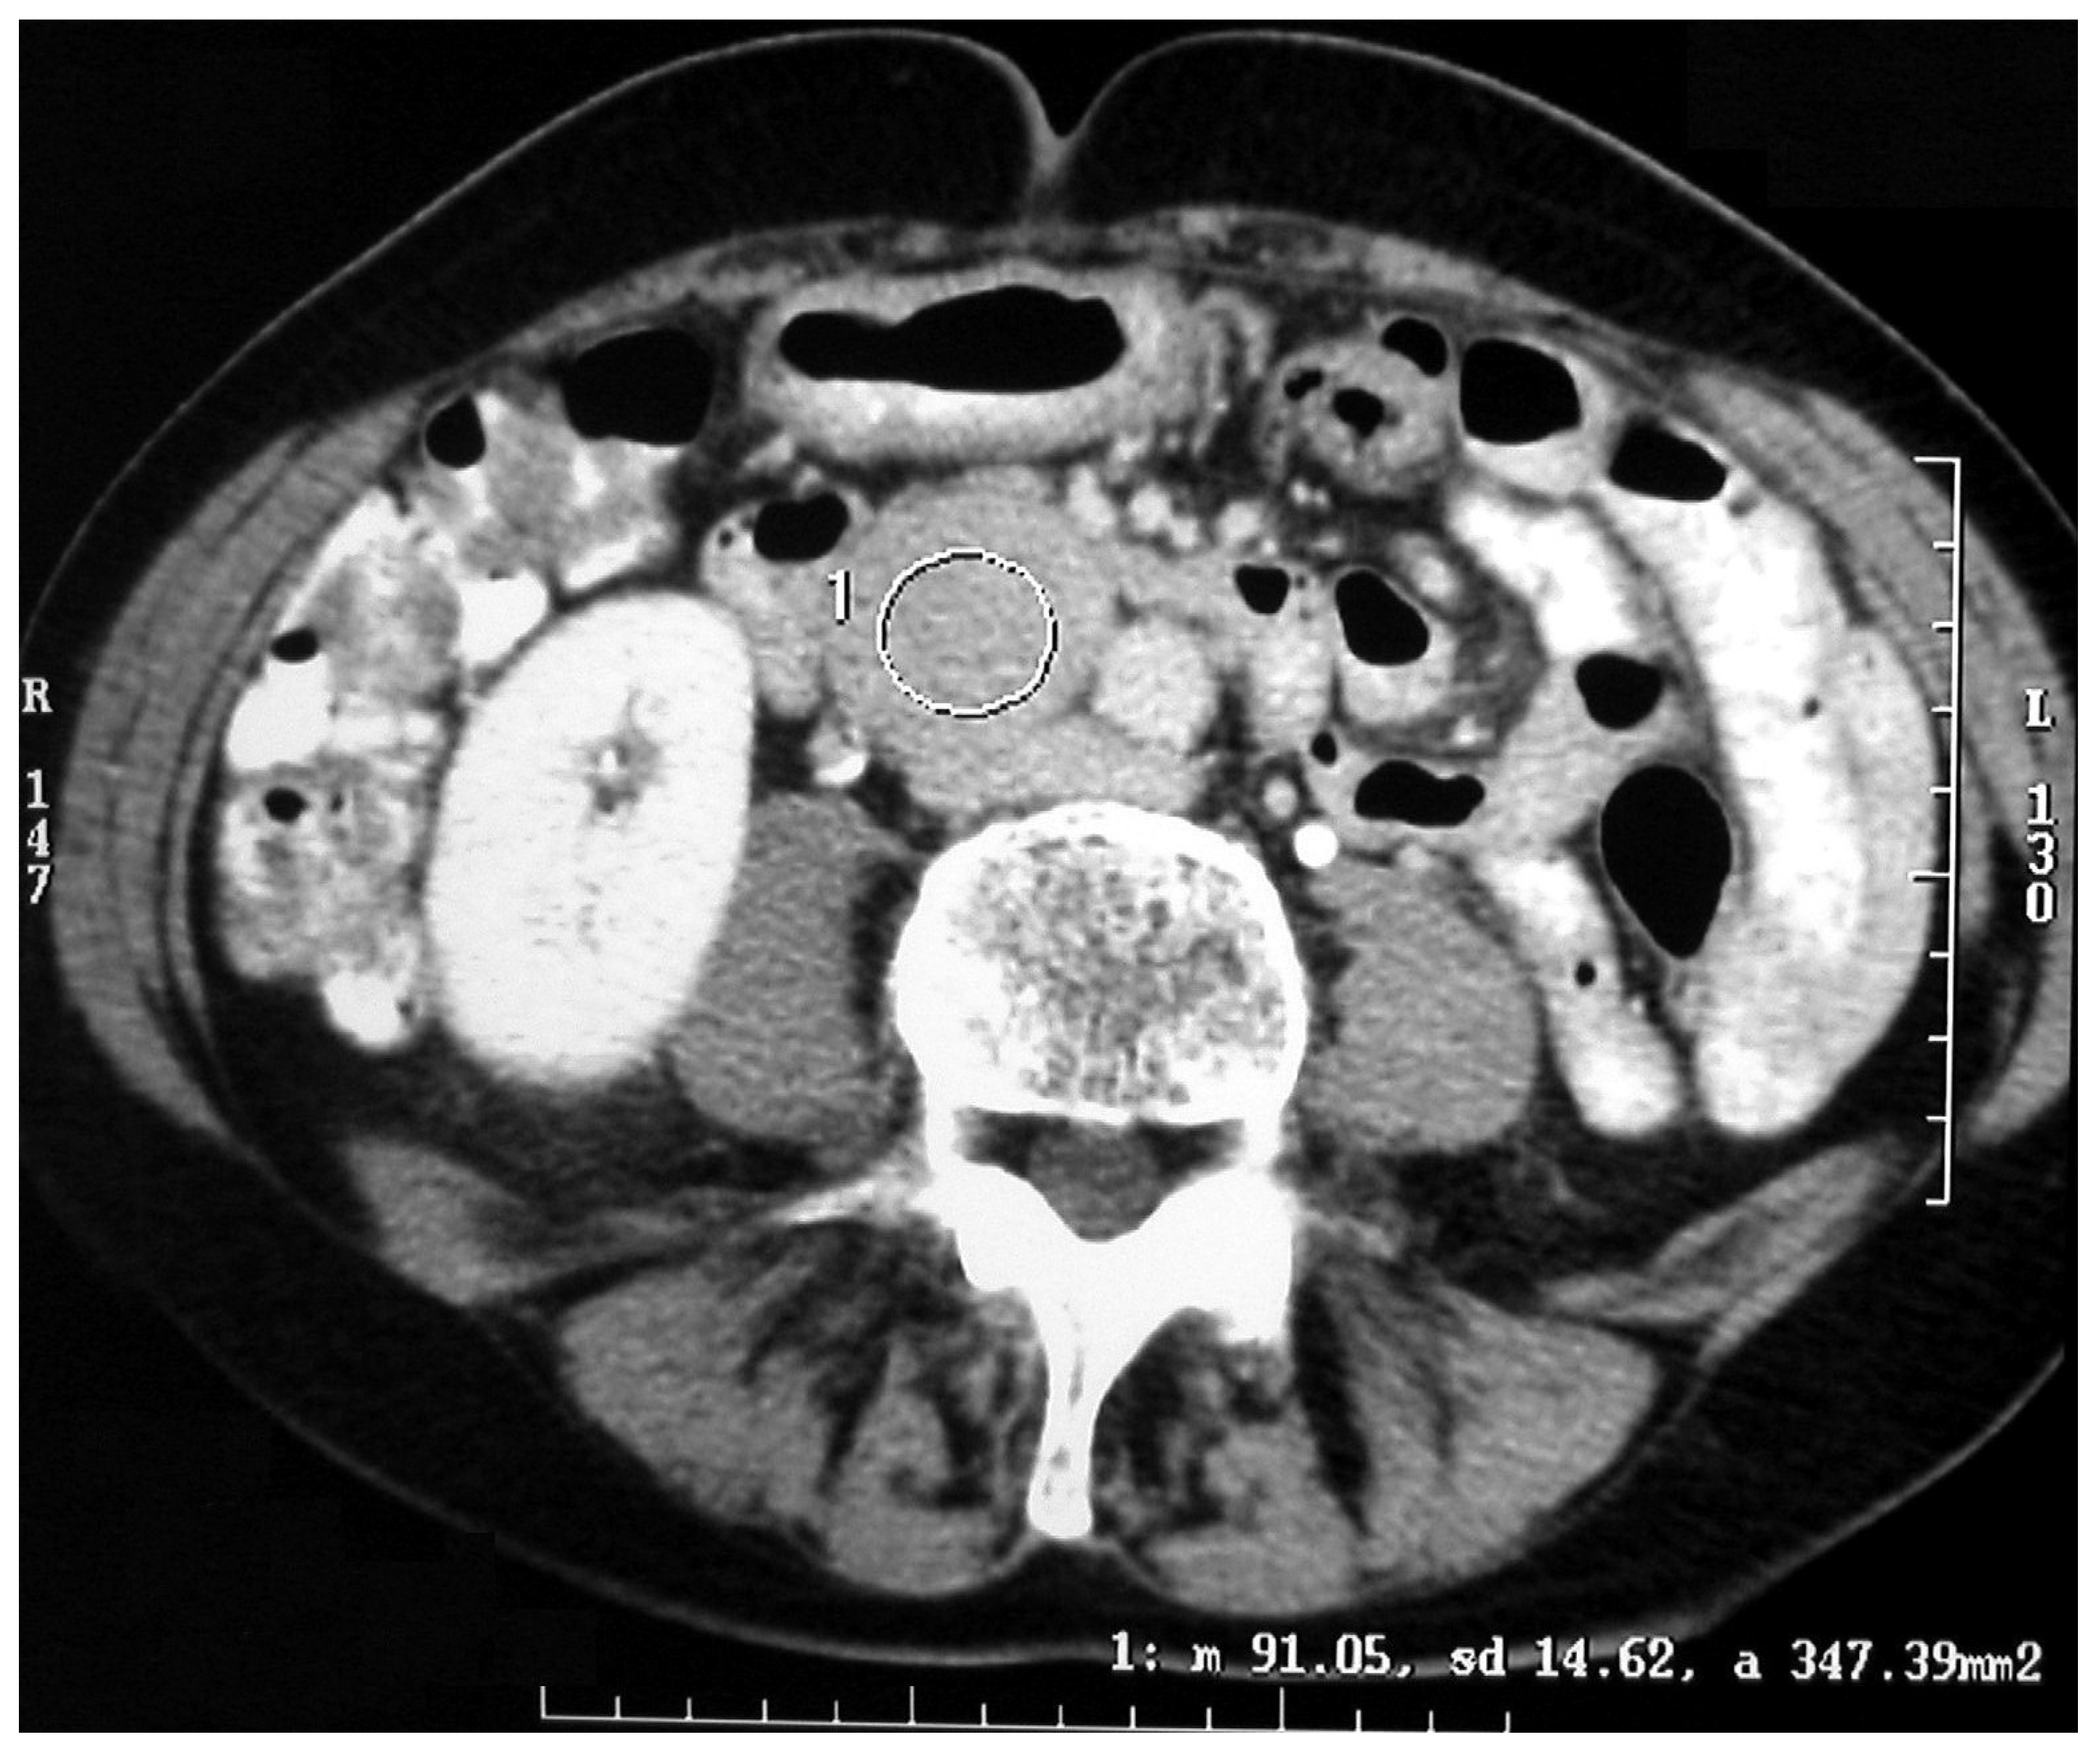

All operations were performed by the same endocrine surgical team. The surgical approaches chosen were laparoscopic excision with transperitoneal approach and abdominal laparotomy based on the results of preoperative investigations considering the position of the mass and the bleeding risk. Laparoscopic approach was performed in four cases (30.7%) and abdominal laparotomy in the other nine (69.3%). Combined abdominal and neck surgery was performed in one case of dual-localization PGL: peri-carotidal and para-aortic. In addition, we performed one left adrenalectomy for the excision of a PGL under the left renal vein using surgical laparotomy, and in another case, cytoreductive surgery was carried out due to the intraoperative discovery of carcinosis (Figure 1 and Figure 2). This patient died eight years later, with massive thorax and abdominal metastases. Another patient died three years after the surgical intervention for malignant hypertension due to metastatic PHEO. The follow-ups for the other 11 patients showed them to be free from disease following operation (follow-up time from 1 year to 10 years).

Surgical resection or debulking of primary tumors, although rarely curative even with the complete resection of metastases, is appropriate in select patients with metastatic PPGLs and may prevent local complications and compression and improve quality of life, lowering rates of hormonal morbidity and potentially improving survival [28,29]. In one case, we found peritoneal carcinosis with a peritoneal cancer index of 12 points, involving the pelvic peritoneum and the mesentery of small bowel. A complete cytoreductive surgery was performed, and the patient was free from disease for almost seven years, and after 8 years, he died. Targeted radionuclide therapies (TRTs), immunotherapy and tyrosine kinase inhibitors can also be used either alone or in combination as multimodality therapy [30,31]. Our study has several limitations: first, the retrospective design did not permit us to obtain complete information about genetic mutation; second, the small number of the enrolled patients is limiting, although the rarity of chromaffin tumors should be considered.

Figure 2. Malignant paraganglioma with peritoneal carcinosis.